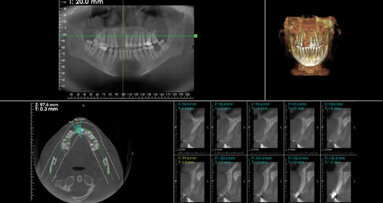

Bone resorption following tooth loss is considered an obstacle for dental implant placement in desired positions, requiring bone augmentation procedures. ...